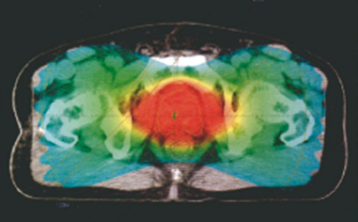

・3D CRT 前立腺三次元原体照射